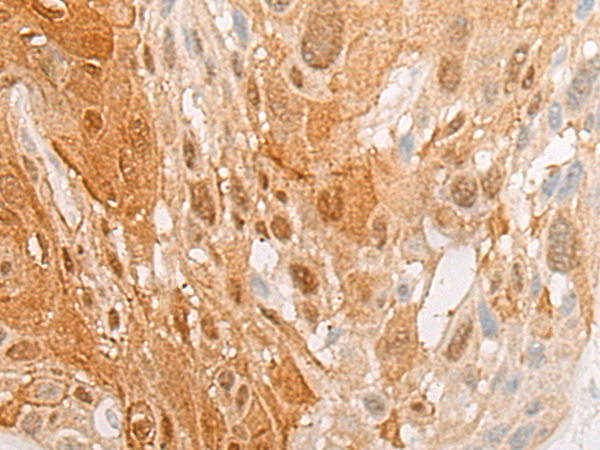

ELISA, IHC |

IHC positive control: |

Human esophagus cancer; |

IHC Recommend dilution: |

25-100 |